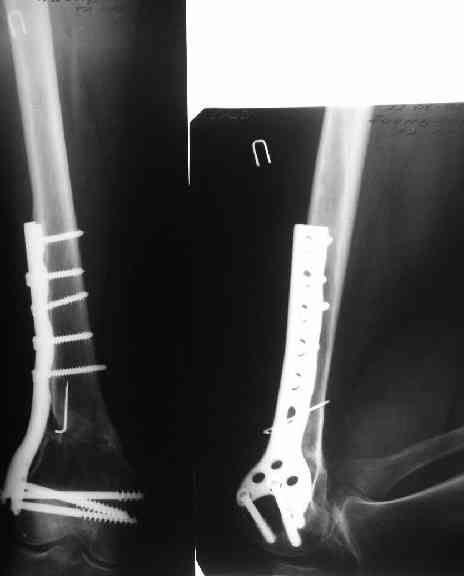

27 марта выполнено удаление блокирующих винтов (сломанный винт пришлось высверливать цапфен-бором), сломанного штифта (дистальный фрагмент удален через канал, образованный разверткой из коленного сустава - image 4),

рассверливание костно-мозгового канала, реостеосинтез штифтом UFN (при проведении штифта в дистальном отломке мы использовали поляризующий винт, диаметр штифта 10 мм). После операции в связи гемартрозом дважды (на 1 и 3 сутки) выполняли пункцию коленного сустава. Сейчас признаков скопления жидкости в полости сустава нет. Послеоперационные рентгенограммы - images 5, 6, 7.